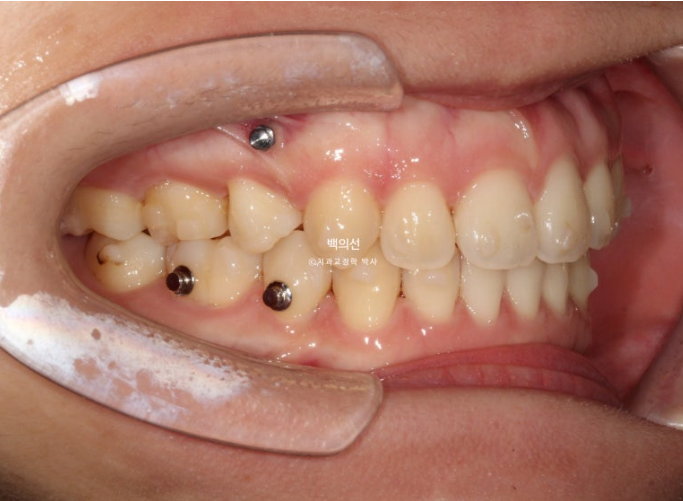

23.01~25.07

맞아진 중심선과 개선된 앞니 개방교합. 이제 면 편하게 끊어 드실 수 있겠어요.

어금니 교합이 기존 3급에서 정1급 교합관계로 바뀌었습니다.

뻗쳐있던 위 앞니가 해소가 되면서 돌출이 해소되었습니다.